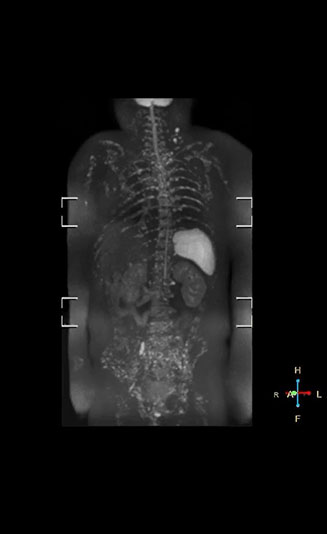

“Before we had Ingenia, clinical adoption was hindered because the exam length of the whole body DWI protocol on our old system was difficult for many patients to tolerate,” says Takanori Naka, MR technologist.

“In our initial whole body DWI, we scanned from the top of the head to the toe in axial orientation. Because that took a lot of time, it constrained the examination to performing only coronal TSE and the axial whole body DWI scans. So, we had to compromise on clinical information to keep the exam to a reasonable length.”

“Fortunately, the Ingenia 1.5T system allowed us to improve our whole body DWI scan and make the exam time more tolerable for patients,” says Mr. Naka.

More clinical information in much shorter exam time

“Once Ingenia was available, our first goal was to shorten the exam time of our scan,” says Mr. Naka. The next goal was to create a protocol that provided more clinical information.

“When we limited the scan coverage to the area from neck to femur, we could fit more clinical information in approximately the same scan time. So, we added coronal mDIXON, sagittal T1-weighted, and sagittal STIR sequences to our examination, instead of performing only axial DWIBS and coronal single-shot TSE scans.”

“With coronal DWIBS, we can perform a full whole body exam, including other sequences, within 30 min.”

Coronal DWIBS is faster and improves image quality

“Switching to coronal DWIBS – rather than axial – further shortens scan time,” says Mr. Naka. “Important is that a dS SENSE factor of 5 shortens exam time while high image quality can be maintained, thanks to Ingenia’s dStream architecture.” He adds that the coronal orientation also avoids artifacts that are specific to combining axial images.

“When we use a coronal DWIBS acquisition, we can perform a full whole body examination, including other required sequences, within 30 minutes,” he says.

“This is considerably faster than the previously used exam with axial whole body DWI, which took more than 45 minutes,” he notes. “A shorter exam is more patient-friendly and allows us to also use it on patients in poor health who would have difficulty tolerating a long exam. Limiting the exam time is also helpful for scheduling, because it fits in a normal single exam timeslot.”